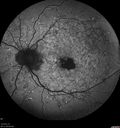

65 year old woman with gradually declining central vision. VA 20/200 in both eyes in the later photos (left eye was better in earlier photos). FAF shows pisciform tri-radiate lesions that are hyper FAF typical of stargardt's fundus flavimaculatus

Stargardt's Macular Dystrophy ABCA4 positivevaatamisi: 536 Fundus Autofluorescence shows central atrophy with Hyper FAF pisciform triradiate lesions. Images show some progression over 3 years of macular dystrophy.00000

Stargardt's Macular Dystrophy ABCA4 positivevaatamisi: 513 Fundus Autofluorescence shows central atrophy with Hyper FAF pisciform triradiate lesions. Images show some progression over 3 years of macular dystrophy.00000

Stargardt's Macular Dystrophy ABCA4 positivevaatamisi: 406 Fundus Autofluorescence shows central atrophy with Hyper FAF pisciform triradiate lesions. Images show some progression over 3 years of macular dystrophy.00000